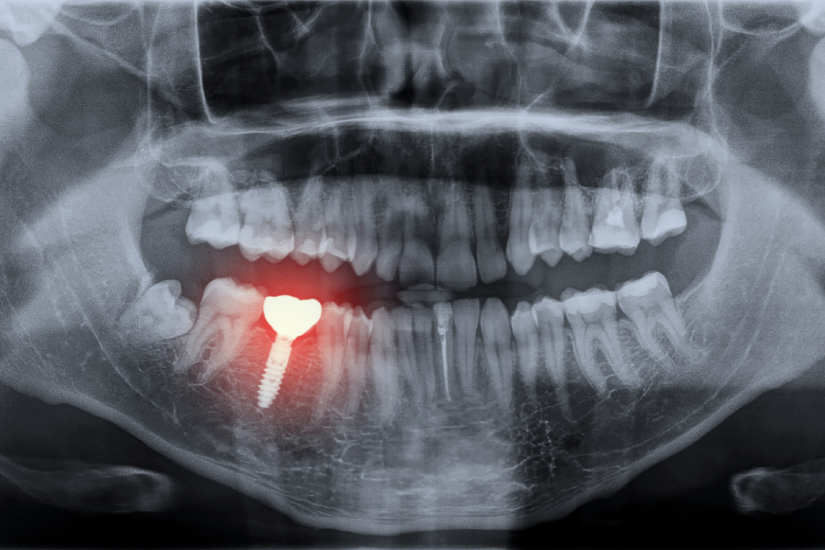

Implantul dentar este un dispozitiv medical, de obicei sub forma unui șurub fabricat din titan sau zirconiu, care se inserează chirurgical în osul maxilar sau mandibular. Acesta are rolul de a înlocui rădăcina unui dinte natural lipsă, servind drept fundație solidă pentru o coroană, o punte sau o proteză dentară.

- Pierderea osoasă vizibilă radiologic: Medicul stomatolog poate observa pe o radiografie că osul din jurul implantului nu se vindecă corespunzător sau chiar se resoarbe.

Infecția în jurul unui implant dentar, cunoscută medical ca periimplantită, este una dintre cele mai serioase complicații. Aceasta este o afecțiune inflamatorie cauzată de bacterii, similară parodontozei, dar care afectează țesuturile moi și dure din jurul implantului.

Cauza principală a infecției este acumularea plăcii bacteriene, favorizată de o igienă orală precară. Alți factori de risc includ fumatul, diabetul necontrolat sau un sistem imunitar slăbit. Simptomele includ gingii roșii și umflate, sângerare la periaj, respirație urât mirositoare, gust neplăcut, și, în stadii avansate, secreții purulente și mobilitatea implantului. Netratată, periimplantita duce la distrugerea osului de susținere și, în final, la pierderea implantului.